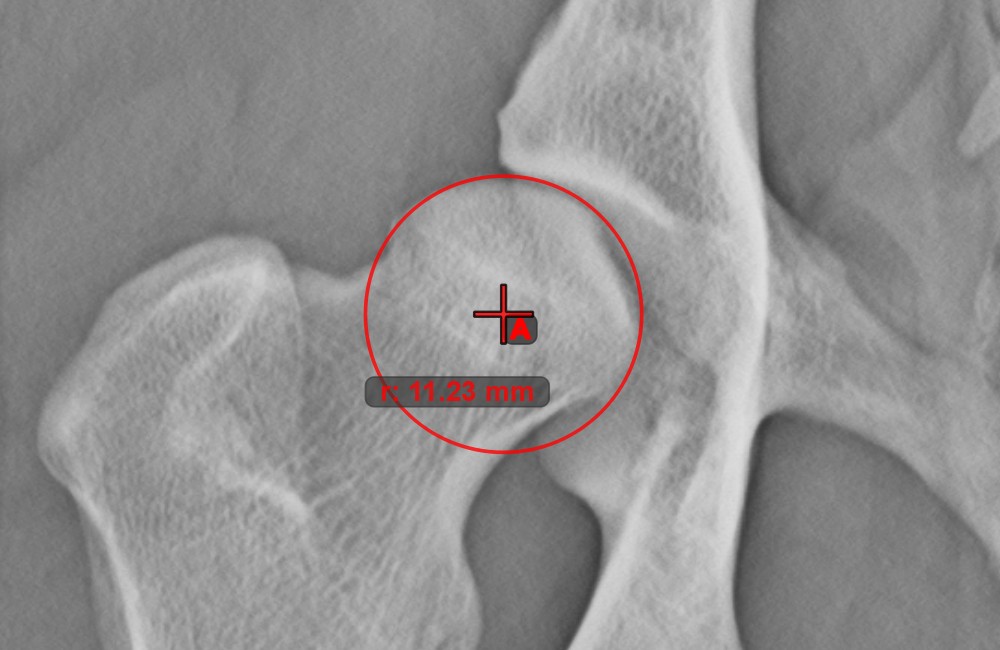

Circle from 3 Points¶

The Circle from 3 Points tool is a simple and effective way to create a circle from just three points.

Start by selecting the tool from the left toolbar and assign it to one of the available mouse buttons. Place the three points of the circle, or select the points from ones available on the scene. The circle will be automatically created based on the position of the three points. The origo of the circle will always be marked with O. The radius of the circle is automatically calculated.

Modify the position of the three points to change the radius of the circle by using the Select/Move Item tool.